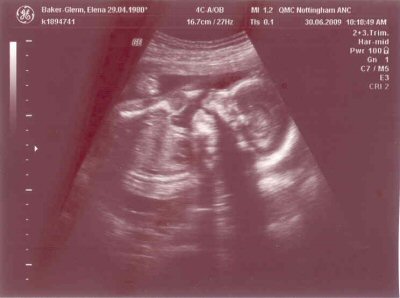

- The scan photos shown below were from the 20 week scan which was done on the 30th June 2009 when the gestational age was 21 + 2 weeks.